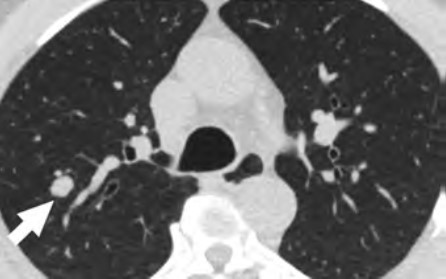

At the individual level, barriers to participation include conflicting personal and health schedules, such as medical appointment times that conflict with working hours, dependent care schedules, understanding the importance of adherence to annual LCS and recommended follow-up (Fig. 4) for the detection of early LC, anxiety and stigma about LC diagnosis, concerns about radiation exposure, and access to primary care services to get LCS referrals [4, 9, 10, 26].

At the individual level, facilitators of participation for LCS include providing schedule flexibility by offering off-hours appointments during weekends and evenings or collaborating with community organizations to offer resources and promote screening during social events in the communities [28, 33]. Providing transportation to LCS appointments, such as ride sharing or cab vouchers, or providing access to mobile LCS units can assist patients in overcoming transportation barriers that could lead to missed LCS appointments [10]. To improve participation, providers can collaborate with radiology practices in communicating the importance of LCS and can promote follow-up through reminders sent to patients, which have been shown to increase LCS adherence [34]. The ACR National Lung Cancer Roundtable (NLCRT) launched a campaign to decrease the stigma associated with a LC diagnosis and decrease concerns about radiation exposure [35–37]. Increasing access to LCS clinics that offer an integrated approach to LCS in collaboration with primary care practitioners can assist in overcoming barriers related to a lack of access to primary care practitioners [38, 39].

At the community and health care system level, facilitators of opportunities include EMR-based LCS appointment reminders available in multiple languages and through additional services other than patient portals, updating population-level health dashboard alerts of patients who are eligible or overdue for LCS under the new USPSTF guidelines, and creating system-based alerts to notify providers about newly eligible patients [10, 34]. Studies that have evaluated LCS adherence rates, patient characteristics associated with adherence, and diagnostic testing rates after screening revealed that underrepresented racial/ethnic minority populations and individuals who currently smoke are less likely to remain in the program [32]. Patients who undergo LCS and are currently smoking can benefit from the integration of smoking cessation counseling services into part of their LCS encounters, and participation in LCS increases adherence to a smoking cessation program [43]. Interventions that combine promoting participation in LCS and connecting patients who are current smokers with an evidence-based intervention composed of a web-based program and text messaging, are examples of a coordinated approach that increases participation in both LCS and smoking cessation [43, 44]. Finally, for assisting patients who have abnormal LCS results, improving telehealth access, increasing the capacity of smoking cessation services, and implementing a tailored approach with multidisciplinary lung nodule clinics for the management of abnormal LCS results and EMR dashboards that automatically track adherence to follow-up and outcomes can provide a system-based care coordination that will aid these patients in accessing LC care [38, 45–47].